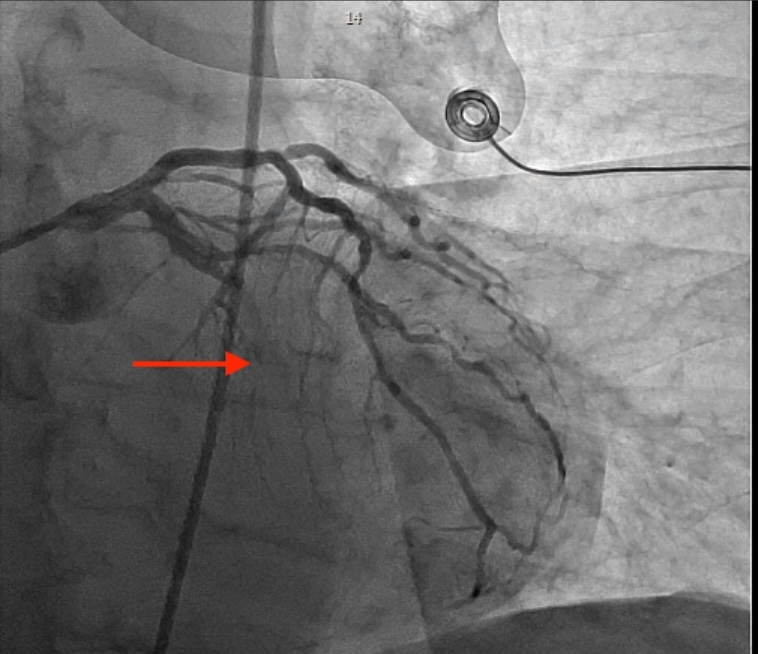

CT angiography revealed bilateral pulmonary emboli (PE) with right heart strain. Emergent coronary angiography showed occlusion of the left circumflex artery, which was successfully stented. Pulmonary thrombectomy was performed the following morning with effective clot extraction. Despite aggressive management, the patient developed progressive renal and hepatic failure with worsening lactic acidosis. Abdominal CT revealed extensive bowel ischemia due to acute mesenteric embolism. Transthoracic echocardiography with bubble study confirmed the presence of a patent foramen ovale with right-to-left shunting, consistent with paradoxical embolism.